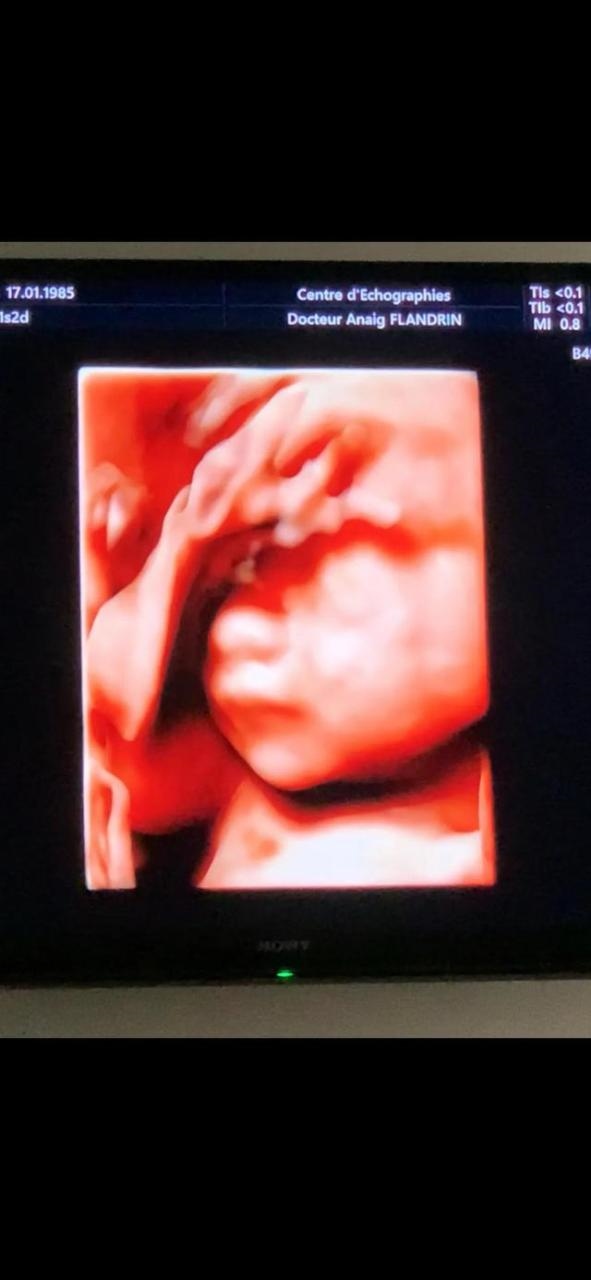

运动:每天做瑜伽 跳芭蕾基础舞蹈,爱爬山,走路。我其实挺后悔 是不是因为孕期特别爱运动 导致我的女儿特别爱动 爱爬,我每天都是跟着她后面跑。下面是我女宝宝在我肚子里的时候 之一次见面就对我们笑还和我们打招呼: